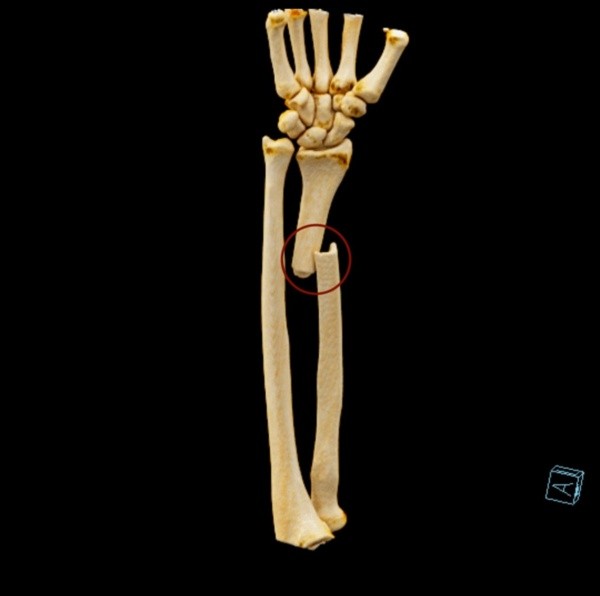

VEJA IMAGENS DA TOMOGRAFIA PRÉ-OPERATÓRIA E DAS RADIOGRAFIAS PÓS-OPERATÓRIAS:

Como ficou o braço do jogador após a fratura (Foto: Divulgação)